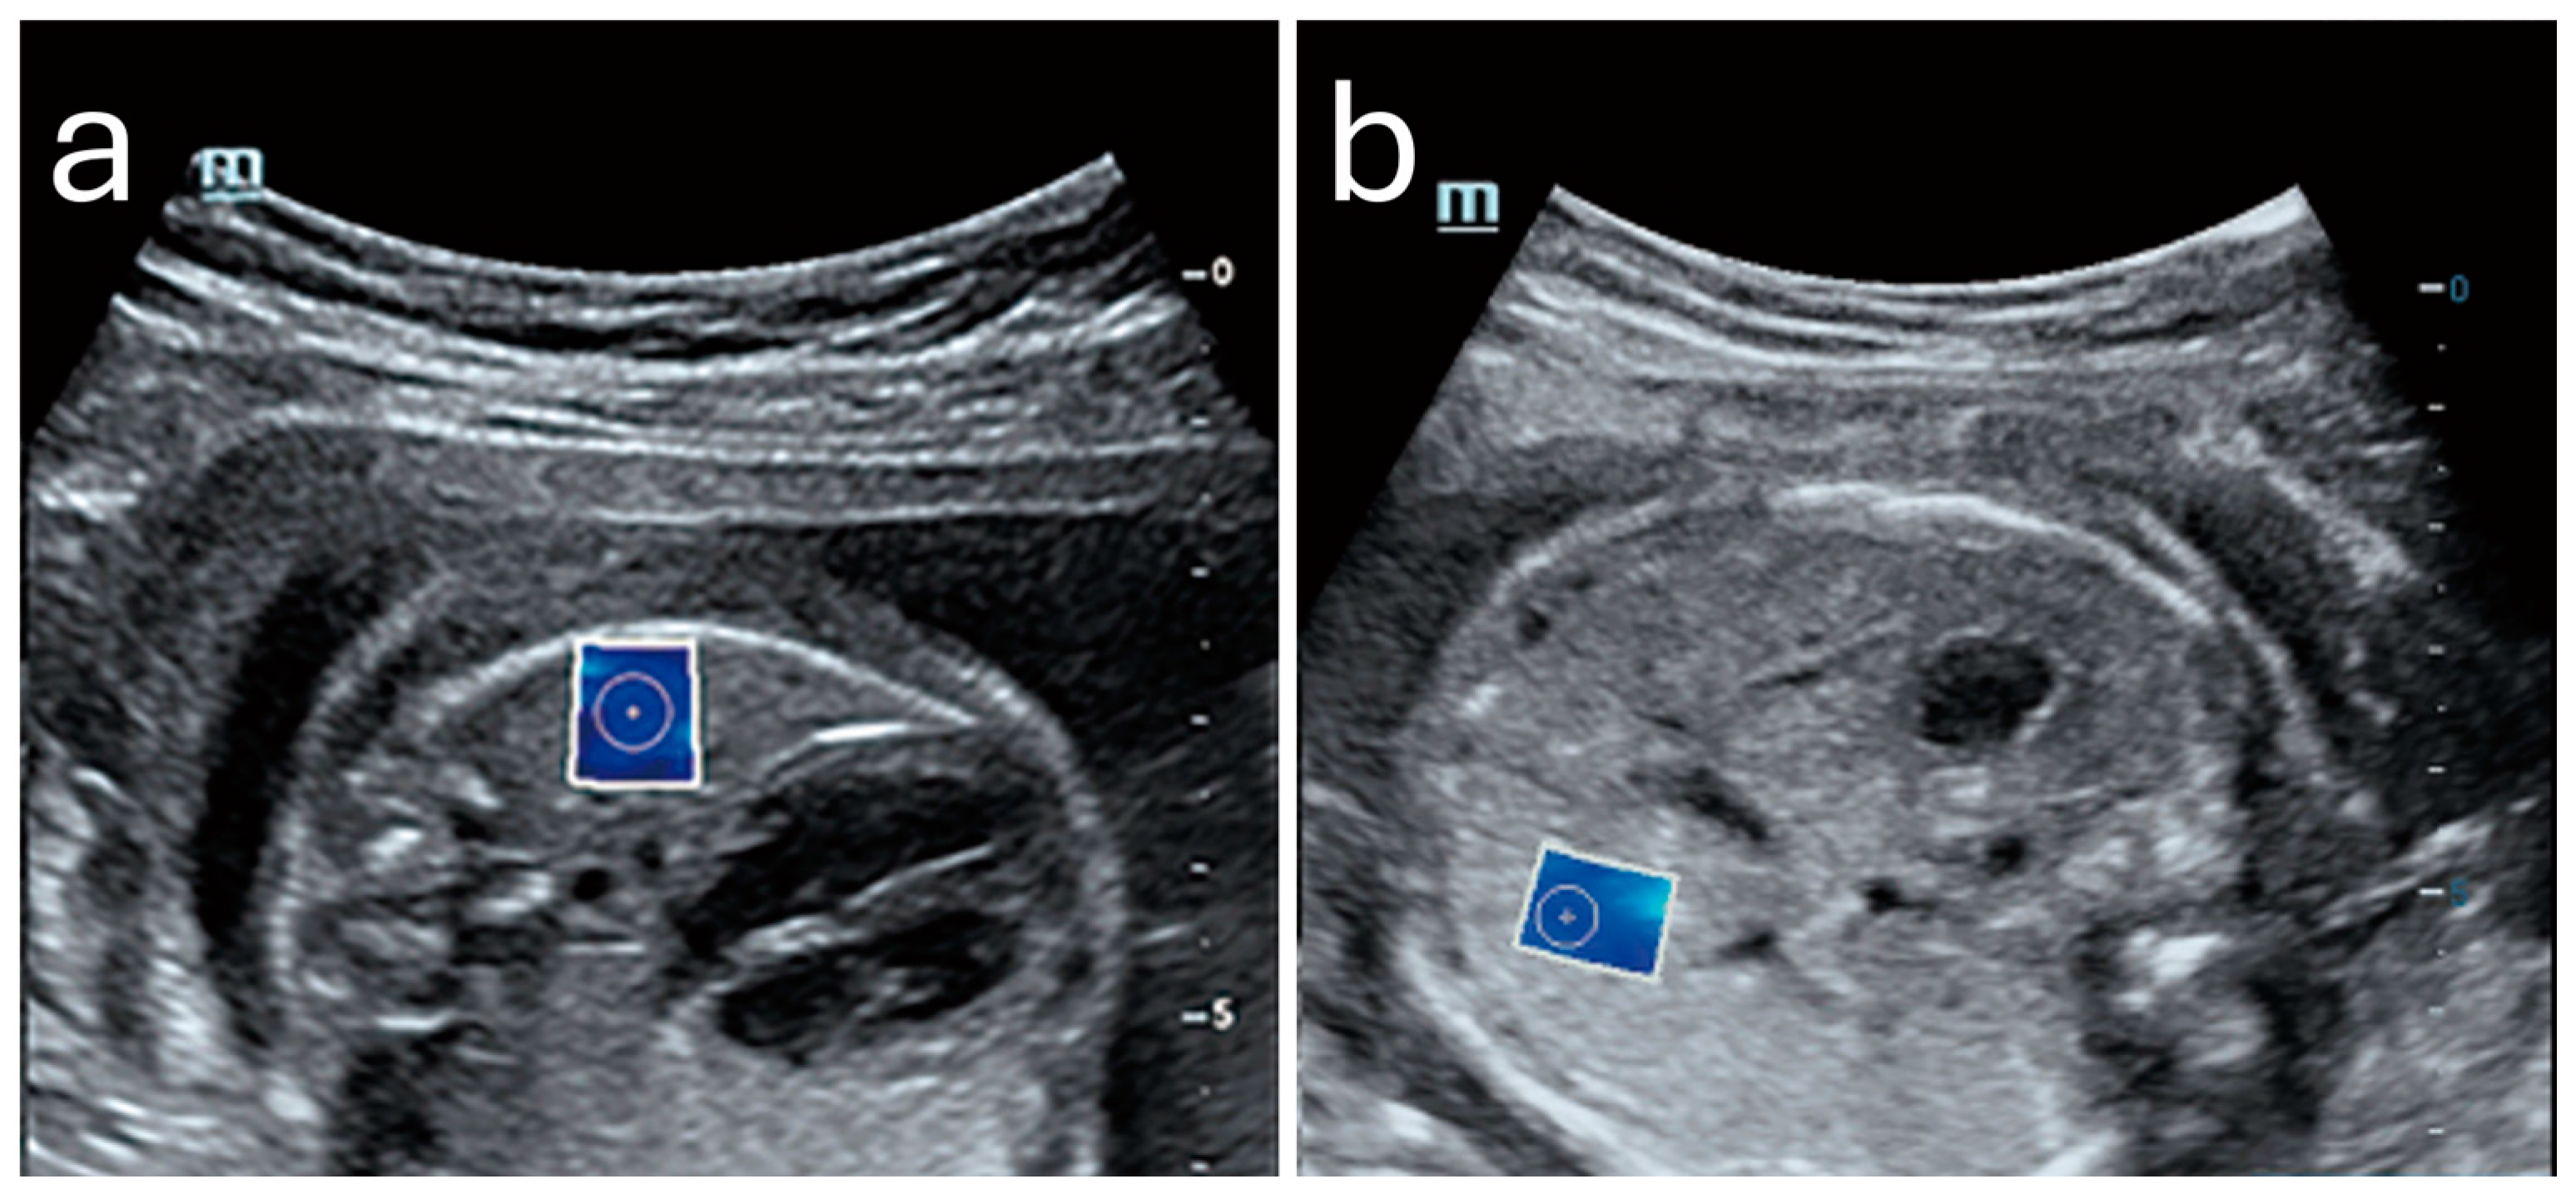

Elasticity in the PFM enables them to respond dynamically to increased abdominal pressure and other physical stresses. For instance, during actions such as the Valsalva maneuver or maximal contraction, the LAM and EAS demonstrate considerable elasticity, which provides resilience against deformation (Figure 3) []. This quality is particularly critical for maintaining the integrity of the pelvic organs and facilitating controlled movement.

Figure 3. Shear wave elastography of the levator ani muscle at rest (a) and during a Valsalva maneuver (b). Image adapted from Gachon et al. [] under a Creative Commons Attribution 4.0 International License. Changes were made to resize and adjust the images.